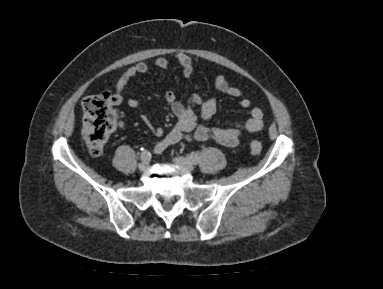

Мультиспиральная компьютерная томография органов малого таза включает в себя исследование женских половых органов (матка, яичники) или мужских половых органов (предстательная железа, семенные пузырьки, семявыносящие протоки), а также мочевого пузыря с мочеточниками на видимом протяжении, прямой кишки, тазовой брюшины, лимфатических узлов, мягких тканей малого таза.

Нативная компьютерная томография таза проводится без использования контраста. Однако при подозрении на патологические изменения со стороны органов мужской или женской половой сферы, мочевыделительной системы, прямой кишки или окружающих мягких тканей, обязательным является внутривенное введение йодсодержащего контрастного препарата. Контрастный препарат в большей степени накапливается в патологически измененных участках и обеспечивает их яркую визуализацию на фоне здоровых тканей. Это используется для диагностики онкологических заболеваний на ранних стадиях, что имеет решающее значение для жизни и здоровья пациента.

В результате получаются снимки тончайших срезов исследуемой зоны с высокой степенью детализации, на основе которых производится объемная реконструкция органов малого таза, что позволяет проводить точную диагностику. Трехмерные модели дают информацию о пространственном расположении органов и патологических образований, что важно, например, при планировании оперативных вмешательств и в дальнейшем при оценке эффективности операции и проведенного лечения.

Мультиспиральная компьютерная томография используется для диагностики аномалий развития, травматических повреждений, воспалительных заболеваний и опухолевых процессов органов малого таза. Преимуществами данного исследования является высокая скорость сканирования и доступная цена. Однако в ряде случаев может быть более предпочтительно выполнение магнитно-резонансной томографии, которая обладает высокой чувствительностью и информативностью для обследования органов и мягких тканей малого таза. В клинике «Доступная медицина» МРТ малого таза можно пройти на нашем современном оборудовании экспертного уровня.